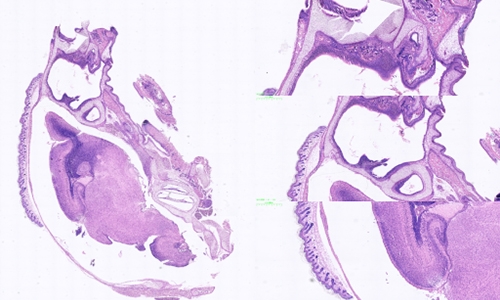

动脉粥样硬化(Atherosclerosis)是一种常见的慢性血管疾病,其病理过程涉及多种细胞和分子机制,对于人类健康造成了重大威胁。为了更好地